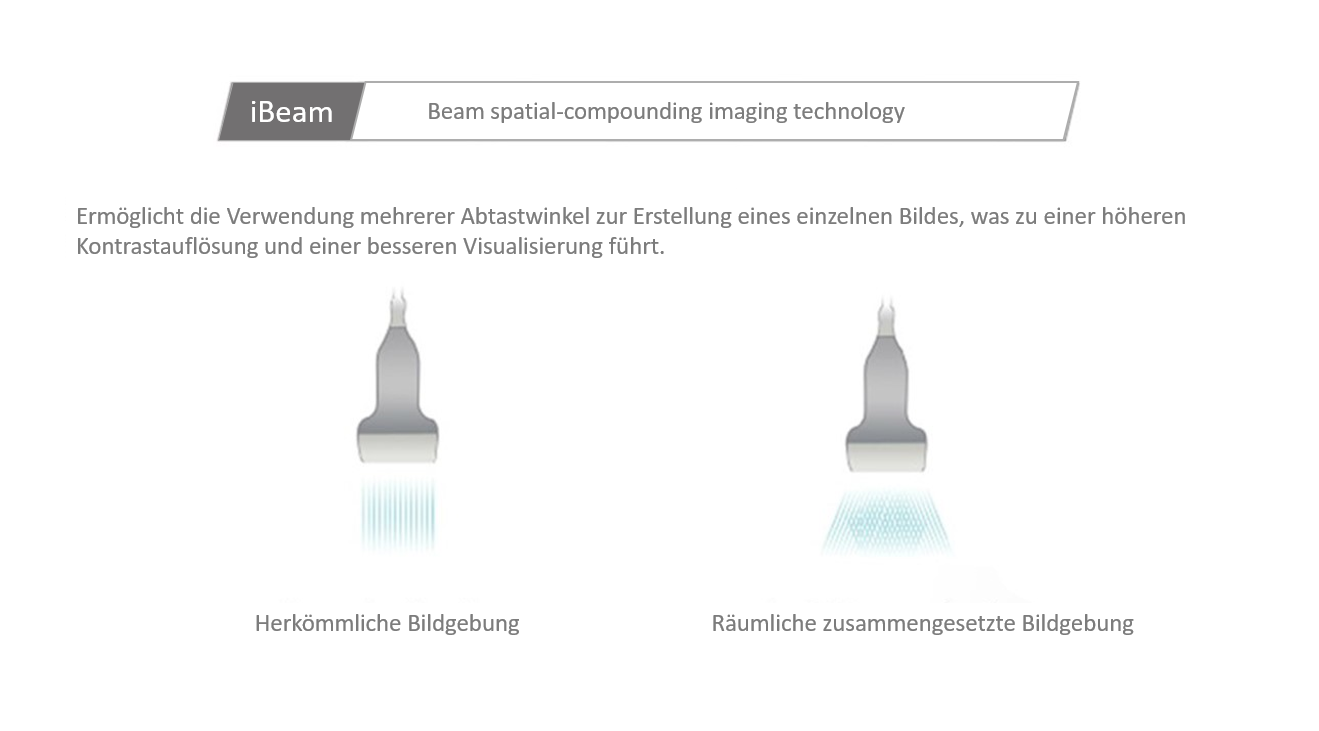

Der Einsatz anerkannter Bildgebungstechnologien macht das DC-30 mit Full HD sehr leistungsstark und hochwertig. Sie sind erfolgreich aus etablierten Ultraschallsystemen migriert worden. Eine clevere Kombination von Ultraschallsonden mit spezialisierten Schallk?pfen unterstĂŒtzt erstklassige Ergebnisse in einem breiten Anwendungsspektrum. Mit Hilfe der Breitband-Schallk?pfe l?sst sich eine Vielzahl an Patiententypen erfolgreich untersuchen. Diese bew?hrten Ultraschalltechnologien sorgen fĂŒr eine h?here Diagnosequalit?t:

- iBeam (Spatial-Compounding)